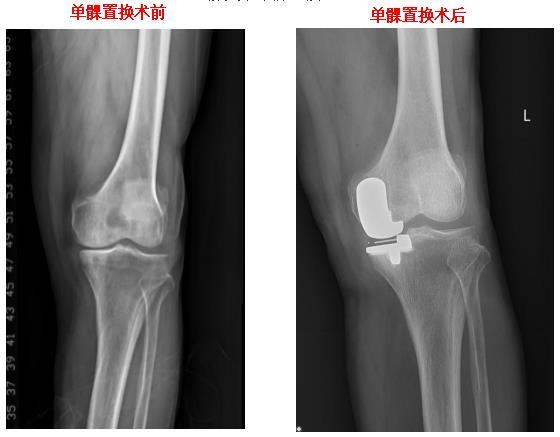

膝关节单髁置换

膝关节表面置换